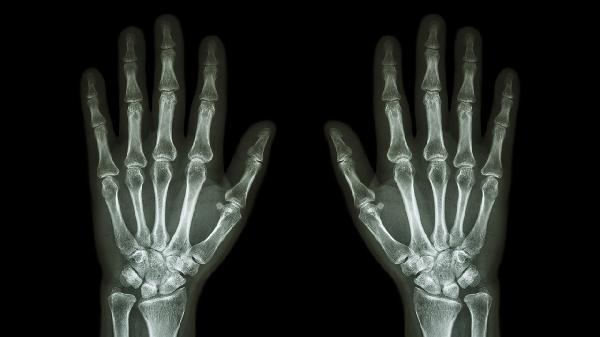

两只手大拇指关节疼痛可能与腱鞘炎、骨关节炎、类风湿关节炎、痛风性关节炎、外伤等因素有关。该症状通常表现为关节肿胀、活动受限、晨僵或压痛,需结合具体病因采取针对性治疗。

关节软骨退行性变常见于中老年群体,表现为拇指指间关节僵硬、膨大变形。X线检查可见骨赘形成。建议减少关节负重,配合硫酸氨基葡萄糖胶囊、盐酸氨基葡萄糖片等软骨保护剂,疼痛明显时可短期使用洛索洛芬钠片。